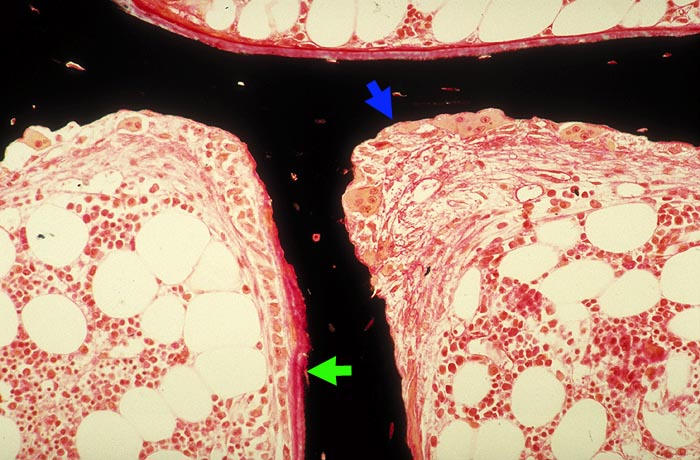

Renale Osteopathie: tunnellierende Fibroosteoklasie, Osteoidose

Stark erhöhter Spongiosaumbau: Resorptionslakune mit Osteoklasten und endostaler Fibrose (Fibroosteoklasie). Osteoblasten- und roter Osteoidsaum (Osteoidose).

Sekundärer Hyperparathyreoidismus bei chronischer Niereninsuffizienz.